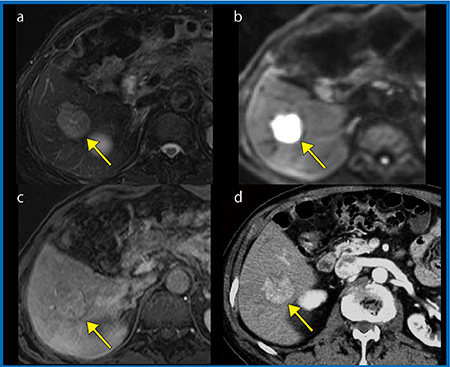

症例1(86歳,男性,肝腫瘍)は,T2強調画像,DWIでは病変を明確に確認でき,分化がある程度進行していると考えられたが(図1a, b),EOB造影MRIでは早期濃染は明確ではなかった(c)。しかし,直近のダイナミックCTでは早期濃染を明確に確認でき(図1 d),EOB造影MRIの動脈相では早期濃染をとらえることができなかったものと考えられる。EOB造影MRIの動脈相のみではなく,直近のダイナミックCTを観察して判断することが必要である3)。

図1 症例1:肝腫瘍(86歳,男性)

a:T2強調画像 b:DWI(b=1000s/mm2)

c:EOB-MRI,arterial phase

d:ダイナミックCT,arterial phase